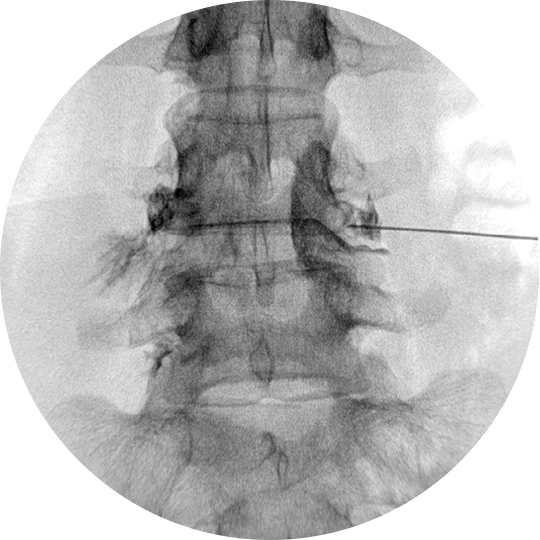

국소마취 후 C-arm 영상 유도하에 고주파 바늘을 신경으로 진입시킨 후 박동성 고주파를 발생시킵니다.

낮은 온도로 신경에 열손상을 주지 않으면서 높은 전압으로 전자기장을 최대화하여 신경생리학적인 변화를 유발하여 통증을 완화시킵니다.